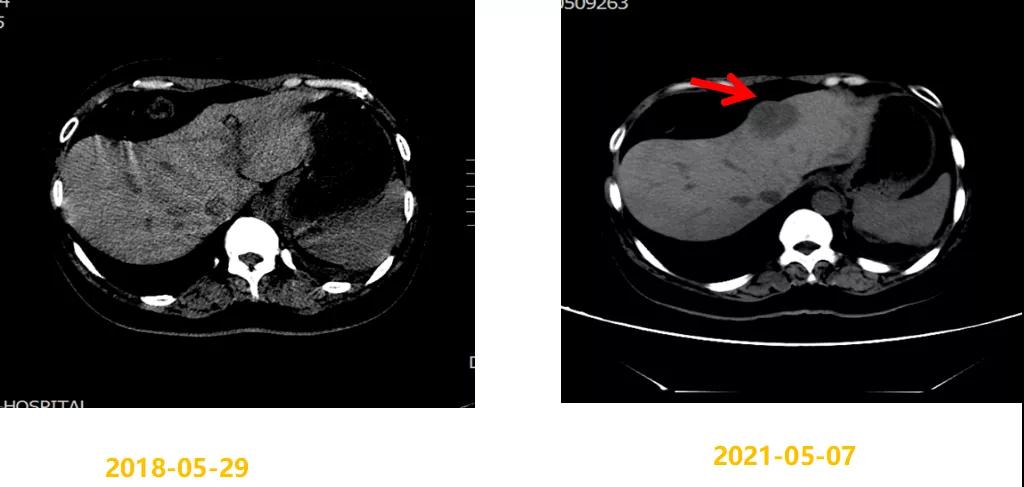

第二次病情进展:2021-05-07 CT示:左侧胸膜略增厚,同前相仿;肝脏稍低密度结节,考虑转移瘤,较前明显增大(大者4.4×3.7cm)。2021-05-08行“肝脏肿物穿刺活检”,病理结果:(肝肿物)符合转移性乳腺浸润性导管癌(组织学Ⅱ级)。免疫组化结果:ER(90%,3+),PR(85%,3+),HER2(1+),Ki-67(40%+)。